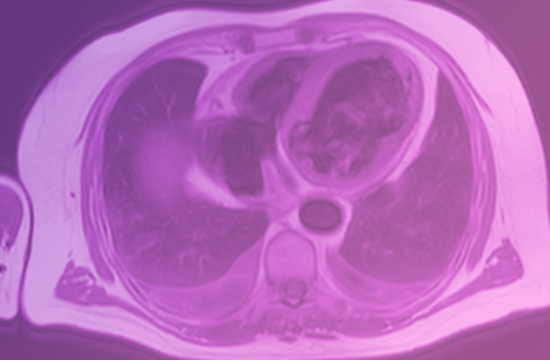

Wie funktioniert MRT im wesentlichen? Und wie wende ich es richtig an? Fragen die ich gerne in meinen Schulungen auflöse und Ihr Wissen vertiefe.